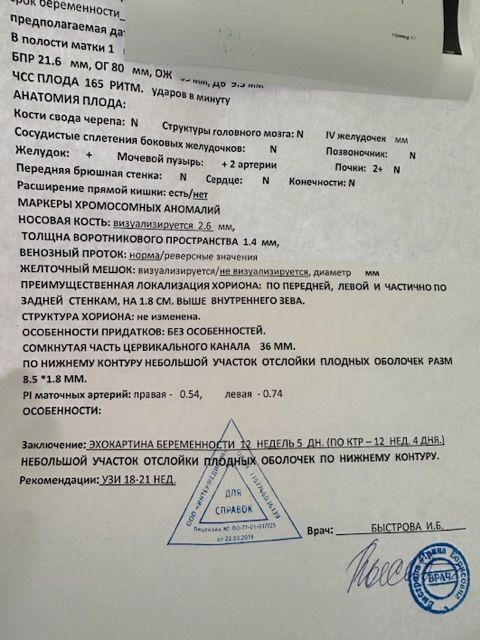

Девочки помогите понять это не критичные размеры отслойки ? Крови не было живот не болит . Как понимать , размер пишет 8,5*1,8 мм

Девочки помогите понять это не критичные размеры отслойки ? Крови не было живот не болит . Как понимать , размер пишет 8,5*1,8 мм